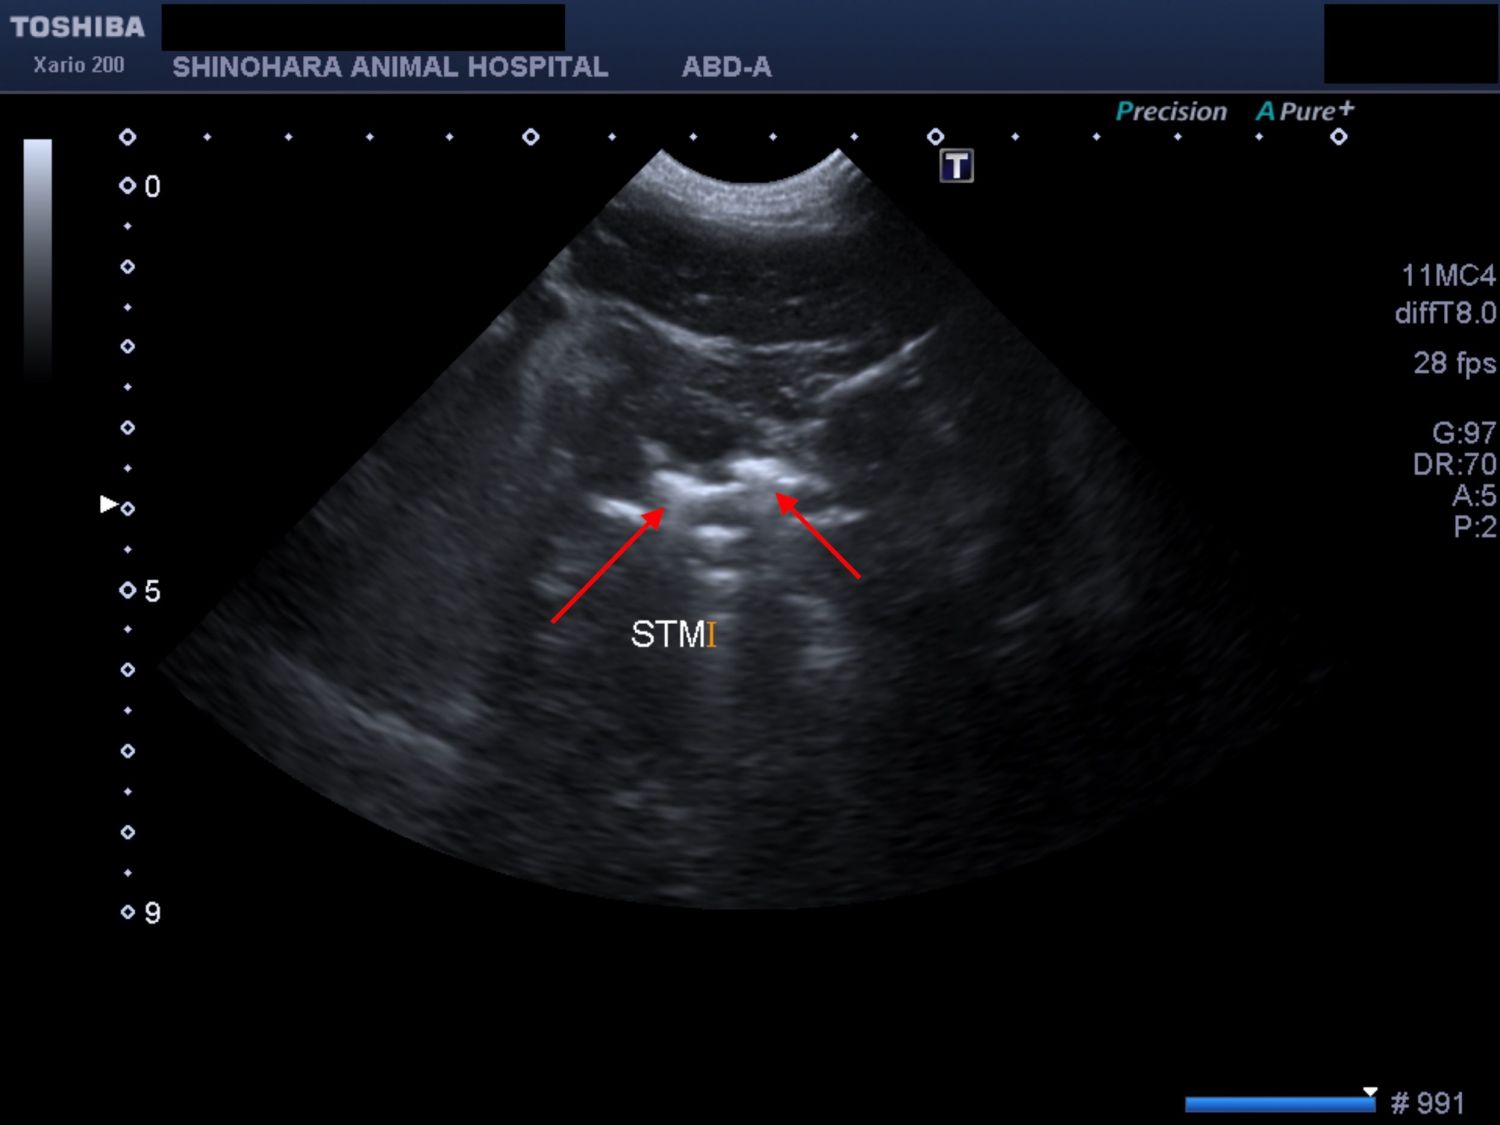

前日の夜間にコーヒーフレッシュを食べ、その後から複数回嘔吐と食欲低下があることを主訴に来院されました。エコー検査で胃内に異物を疑う所見があったため、内視鏡検査を実施しました。内視鏡検査で胃内に大量のコーヒーフレッシュを確認しましたが、あまりにも量が多く内視鏡での摘出は不可能と判断し、そのまま胃切開術を実施しました。コーヒーフレッシュ以外にも、菜箸の破片やスポンジなどが摘出されました。

コーヒーフレッシュの影が映っています(赤矢印)